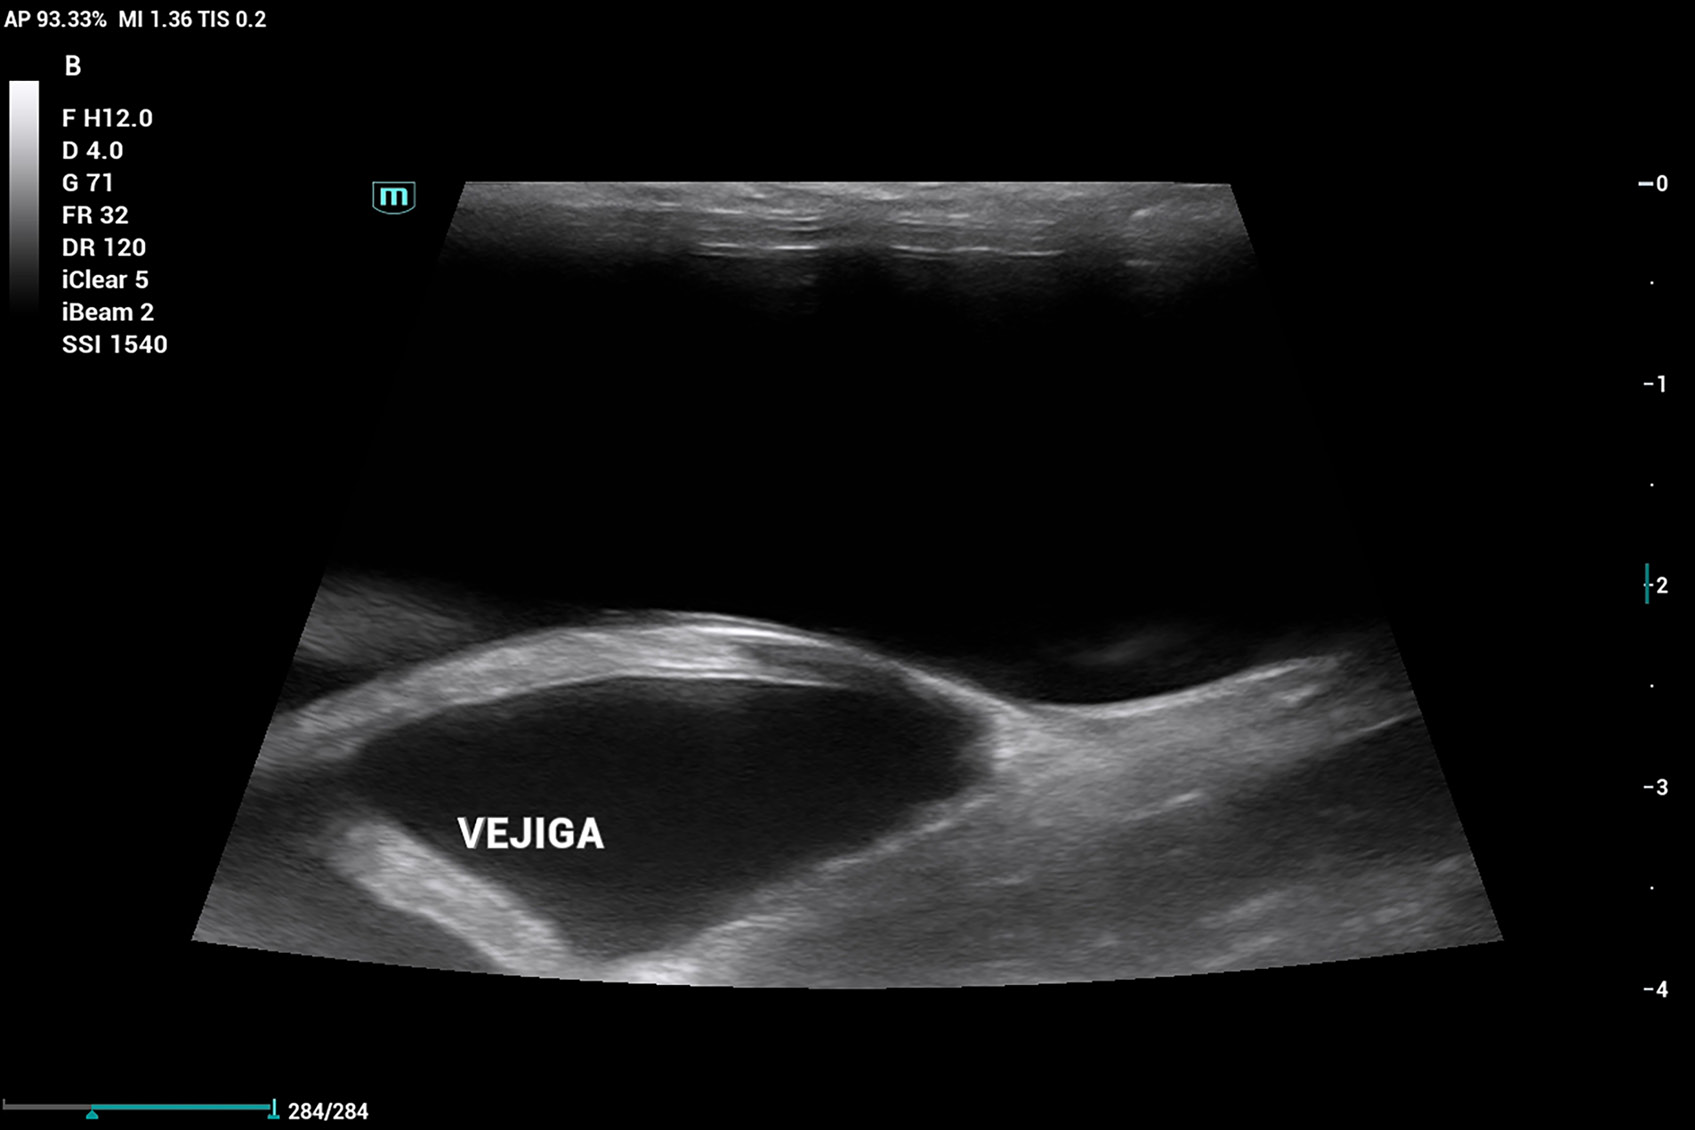

Se realiza ecografía abdominal, que evidencia que aún cuenta con cuernos uterinos (imagen 6), lo que confirma la ovariectomía (no ovariohisterectomía). Por este motivo, se decide enviar una muestra de plasma sanguíneo a un laboratorio externo para evaluar los niveles de 17β-estradiol, dado que en ecografía no se logra distinguir con claridad un remanente ovárico.